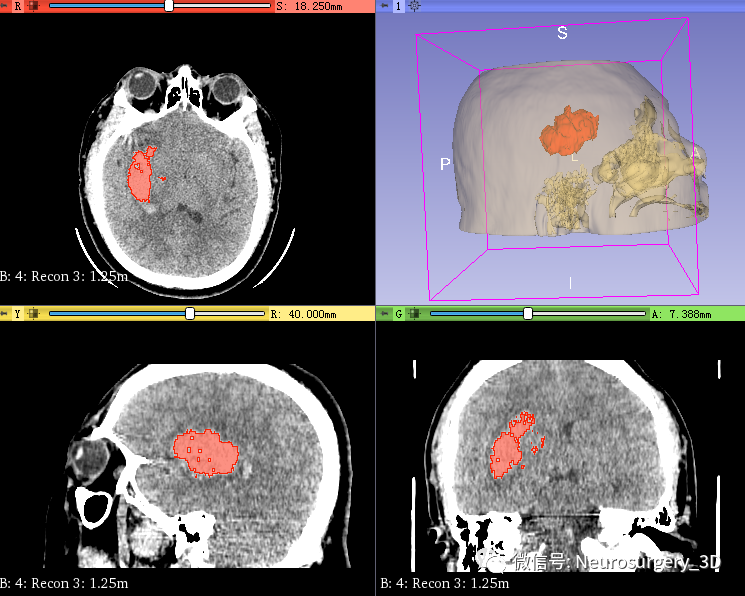

2、可透视化显示颅内血肿形态

3、利用Logical operators逻辑运算模块复制头颅原始模型并扩大。

4、再次利用Logical operators逻辑运算模块,运算后重建出面具三维模型

运算后结果

放大后不同视角观察